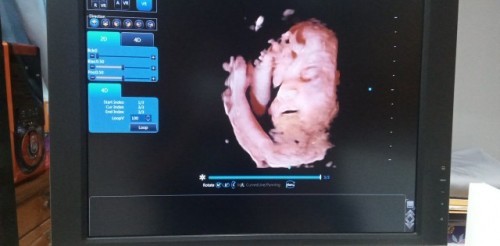

23 กุมภา ให้เห็นแค่ครึ่งหน้ายกขาขึ้นมาปิด